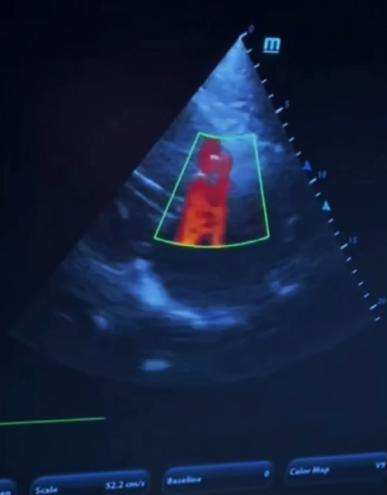

УЗИ сердца или «эхокардиография» - позволяет комплексно оценить жизненно-важные параметры сердца как главного органа и заранее выявить патологии.